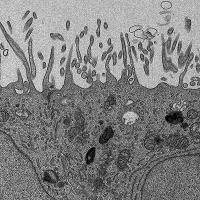

Rod outer segment showing connector

UC Irvine researchers reveal molecular mechanisms of eye disease using cryo-electron tomography

Understanding the key structural determinants of a highly specialized membrane in the eye could lead to new treatments.